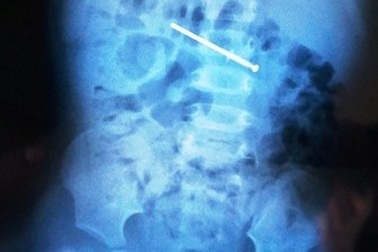

Thợ hồ nhập viện với cây đinh đâm xuyên thành bụngNạn nhân nhập viện trọng tình trạng bị cây đinh đâm xuyên thành bụng nguy cơ gây tổn thương nội tạng, nhiễm trùng ổ bụng. Chỉ vì sơ ý trong lúc làm việc trên công trình đã khiến người thợ hồ gặp nạn.